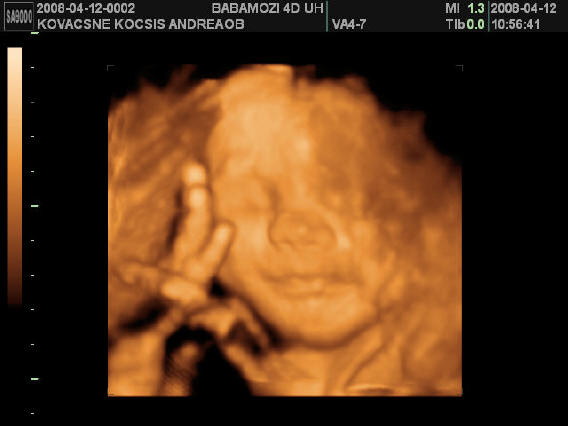

A doki szerint pufók kislány

És egy tappancs 2008.03.08 19:45